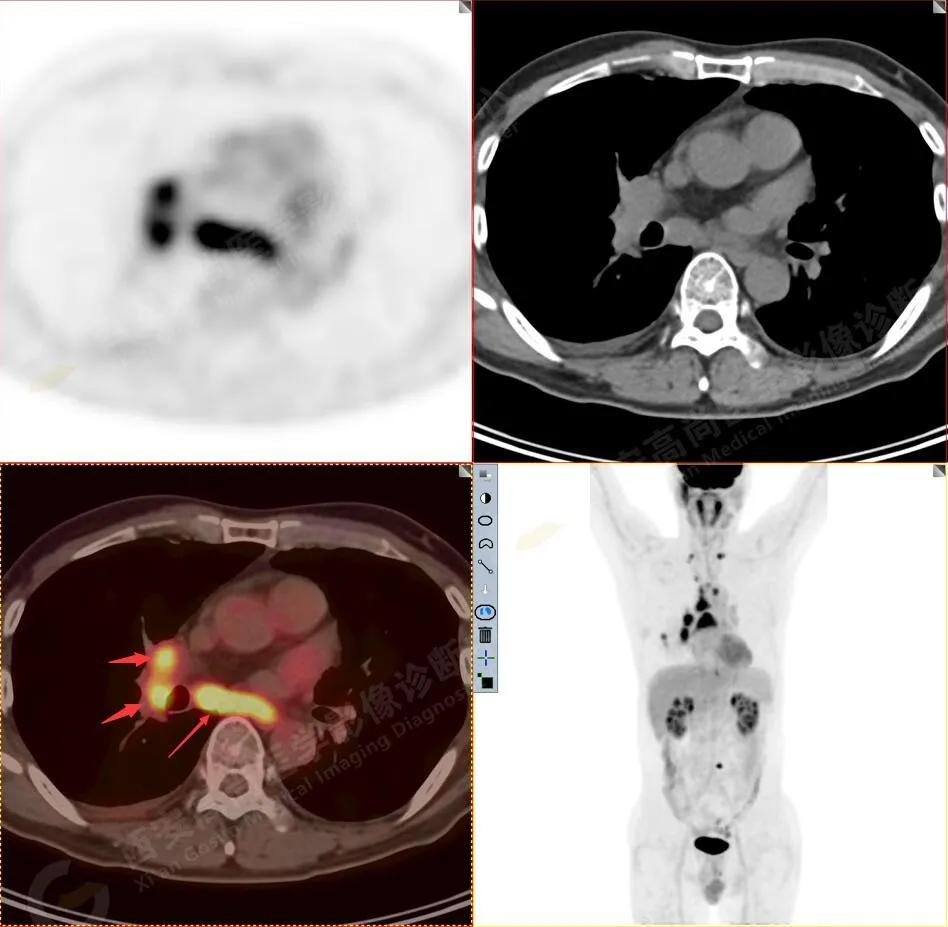

1.以下为肺内原发灶

原发病灶

FDG代谢增高

双测锁骨上淋巴结转移

纵隔(1R\1L组)淋巴结转移

2R组淋巴结转移

4R、3A组淋巴结转移

4R组淋巴结转移

4R组及右肺门淋巴结转移

1.右肺下叶后基底段软组织结节(约1.5cm×1.2cm),与相邻后胸膜分界不清,呈FDG代谢异常增高,结合病理,符合肺腺癌伴邻近胸膜侵犯。

3.右侧肺门、纵隔(1L、1R、3A、4、6、7组)及双侧锁骨上多发肿大淋巴结,呈不同程度FDG代谢异常增高,考虑为淋巴结转移。